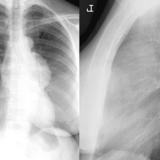

Case 2

Thymoma

Date: 03/17/2004

Views: 5635